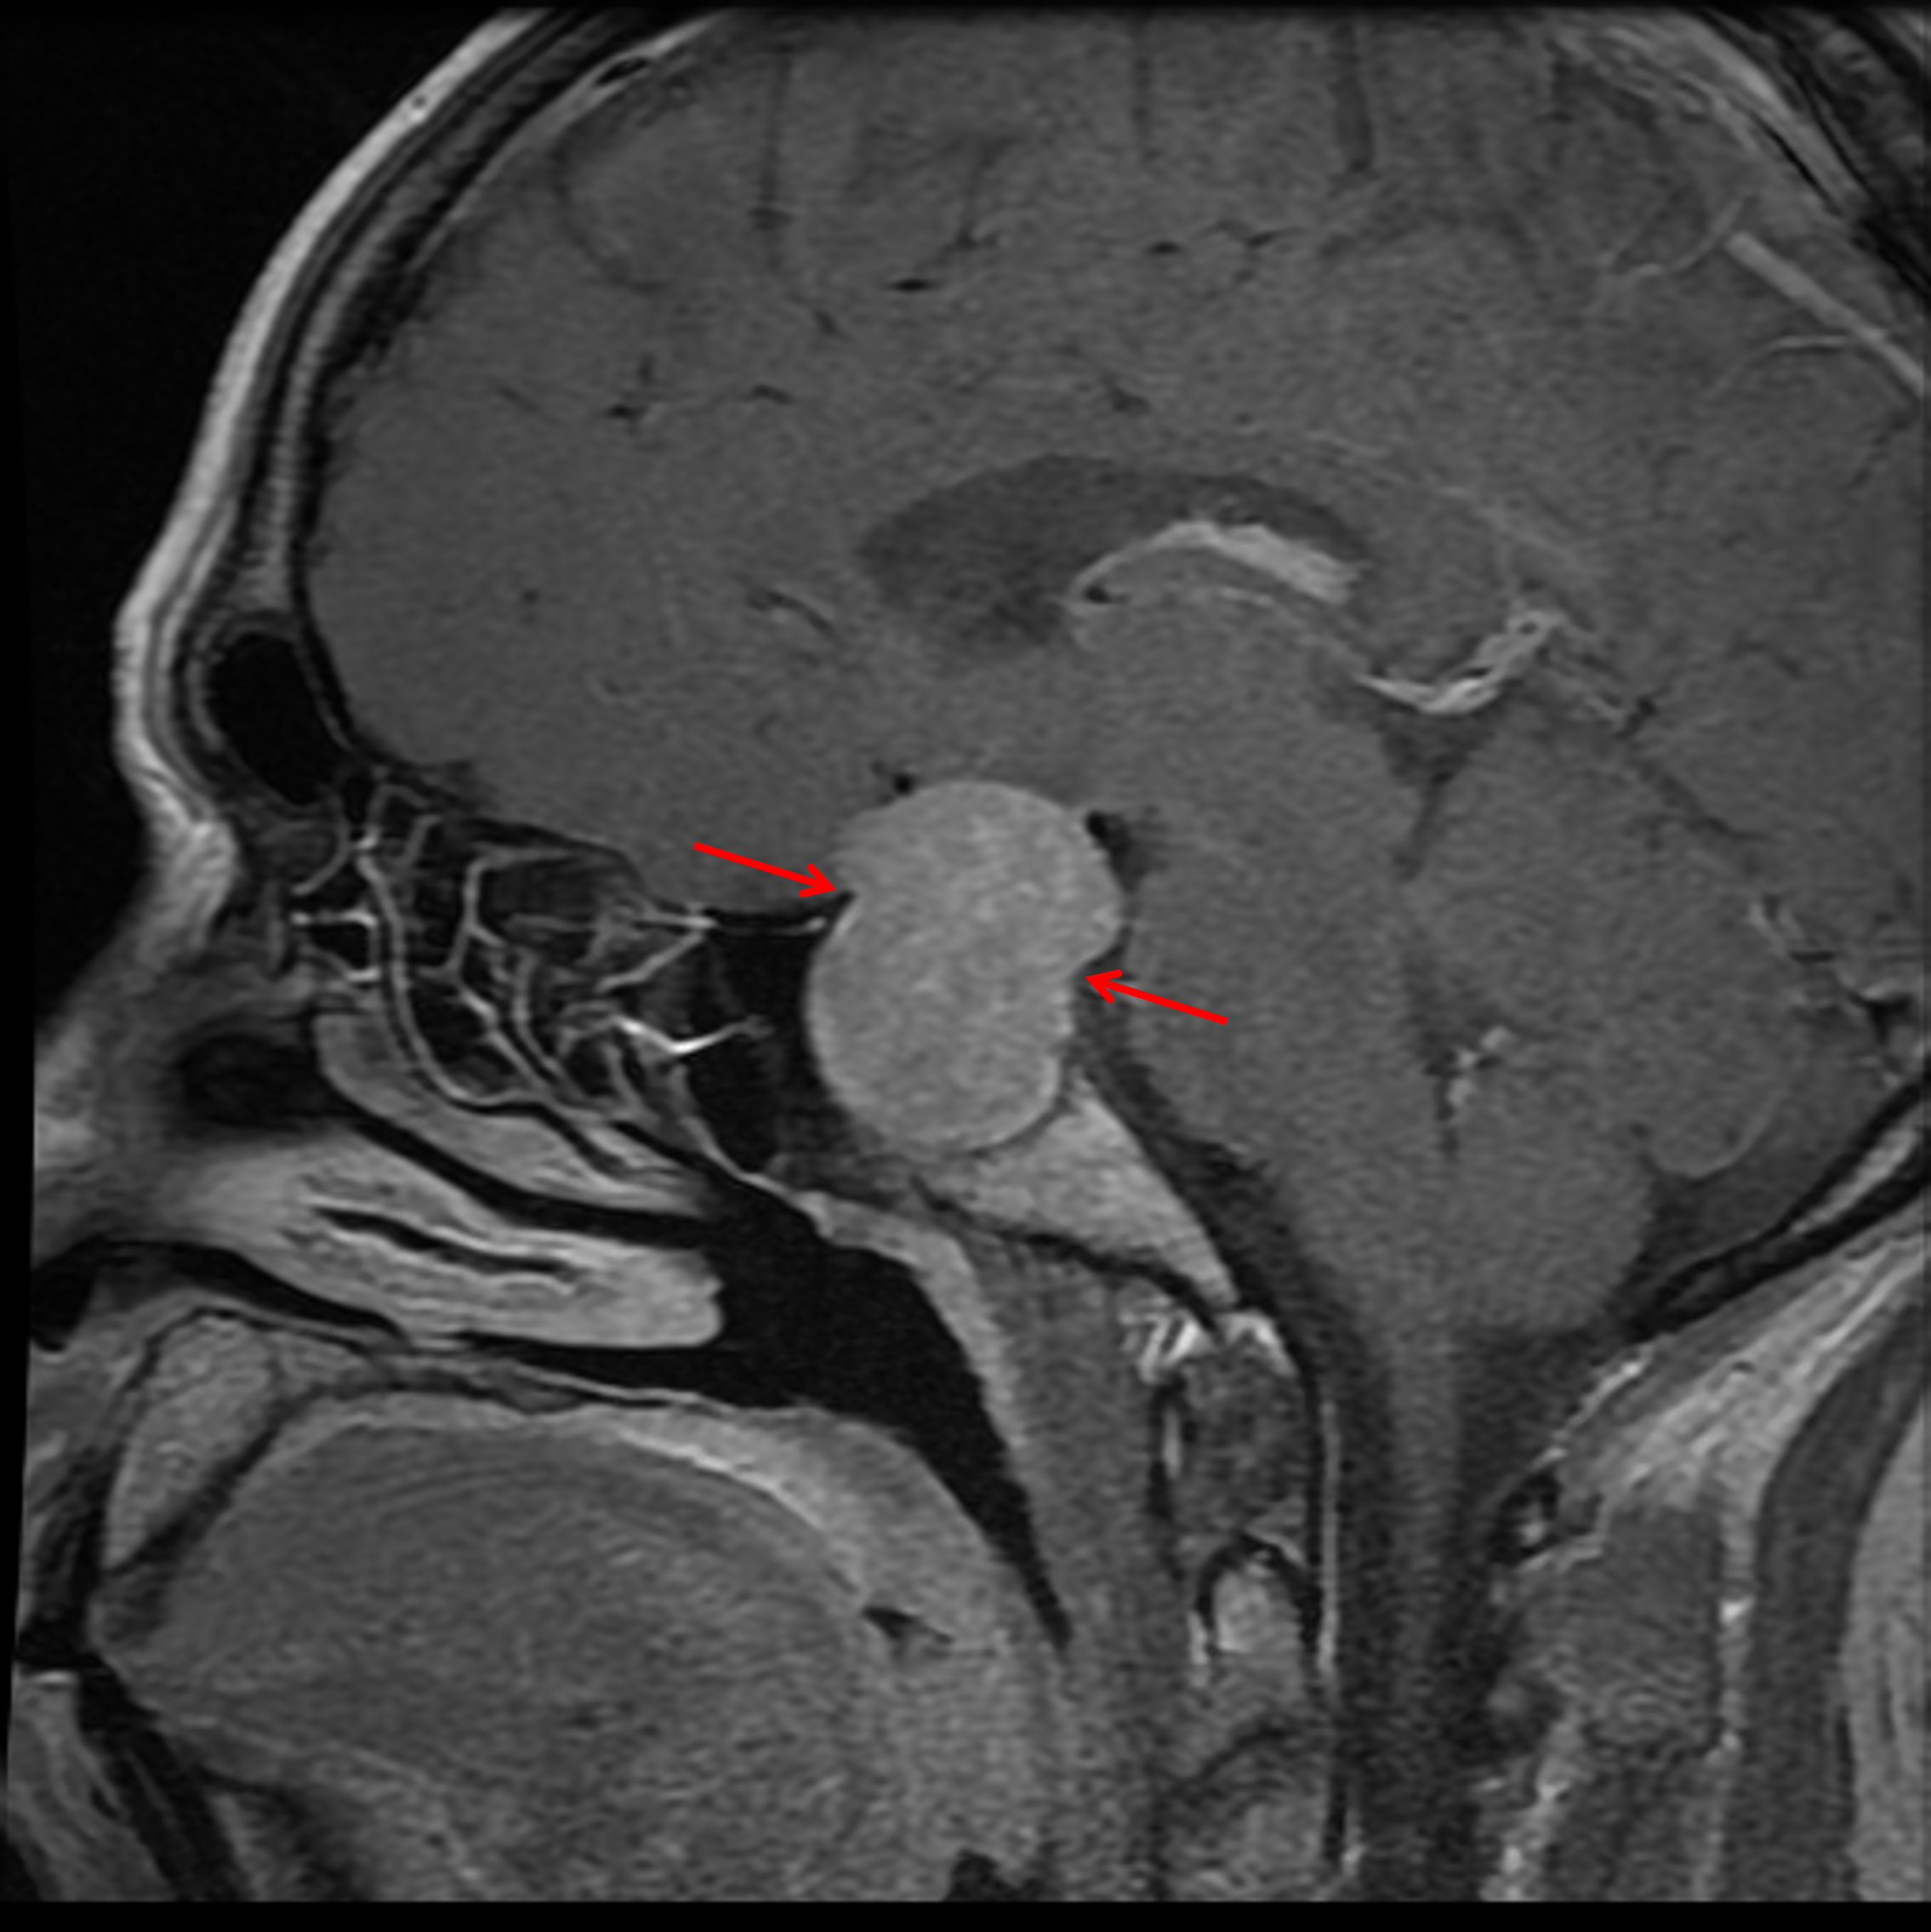

Age: 38

Sex: Male

Indication: Problems with vision

Pituitary macroadenoma